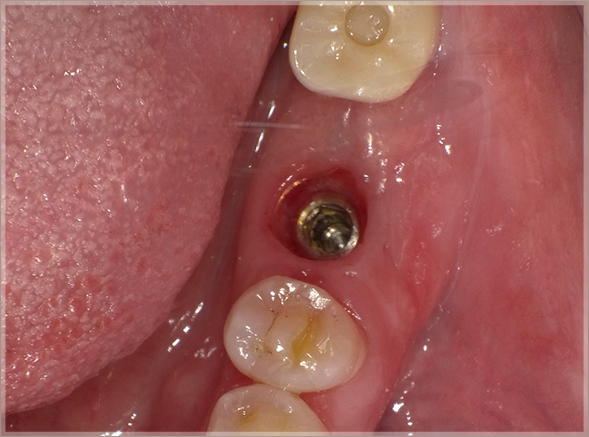

8.補綴を開始します(埋入後61日経過)

⑭埋入後61日経過、補綴開始

⑮オステル値81(ISQ)

オステル値81は、インプラント後の骨と歯肉状態が高く安定していることを示しています。